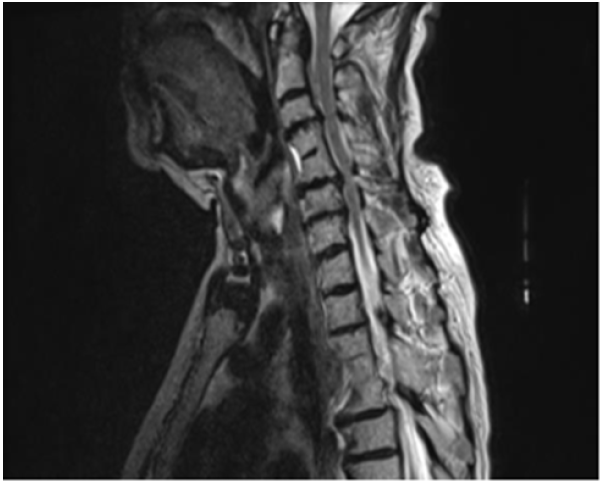

A 76-year-old woman with known hypertension, diabetes mellitus, hypothyroidism was admitted with complaints of increased forgetfulness, urinary incontinence and impaired balance for about 6 years. She was hospitalized with the preliminary diagnosis of Normal Pressure Hydrocephalus (NPH) because of the expansion of periventricular distances in radiological imaging. She was conscious and oriented but had limited cooperation. There was no sign of meningeal irritation and no nuchal rigidity. Her speech was fluent, and she had a complete understanding. Cranial nerve examination was normal. Motor system examination revealed bilateral shoulder muscle strength 3/5, elbow muscle strength 4/5 and wrist muscle strength 5/5. In other words, the patient had proximal dominant muscle weakness on the upper and lower and the appearance of the MIBS. Deep tendon reflexes were normoactive bilaterally; Hoffman sign was positive bilaterally; abdominal skin and jaw reflex were normal. The sensory system examination revealed a superficial sensory defect on the soles of the feet, the cortical sensation was normal, deep sensation in the lower extremity was decreased. Extrapyramidal and autonomic system examination was normal. The cerebellar examination was consistent with motor weakness. She had no ataxia and was spinning in 3-4 steps. Standardized mini-mental test was 22 points out of 30. The CSF dynamic MRI was consistent with small vascular disease and advanced encephalomalacia (Figure 1). On cervical MRI, C4-C5 and D4-D5 vertebrae were fusion with each other, and protrusions accompanied by dorsal osteophytes, spinal cord compression and accompanying myelomalacia were observed in C5-6 and C6-7 (Figure 2). Dementia had been attributed to chronic vascular disease. The current neurological deficit, persistent gait and balance disorder, loss of fine motor skills and bladder dysfunction were thought to be due to advanced cervical stenosis. An elective cervical laminectomy was planned, but it could not be performed due to additional comorbidities. Conservative therapy was suggested. Physical therapy was planned to preserve a range of motion of the upper extremities. Replacement therapy was given for vitamin d deficiency.

Figure 2:Cervical MRI showing spinal cord compression and myelomalacia in C5-6, C6-7 and D4-5 vertebrae.